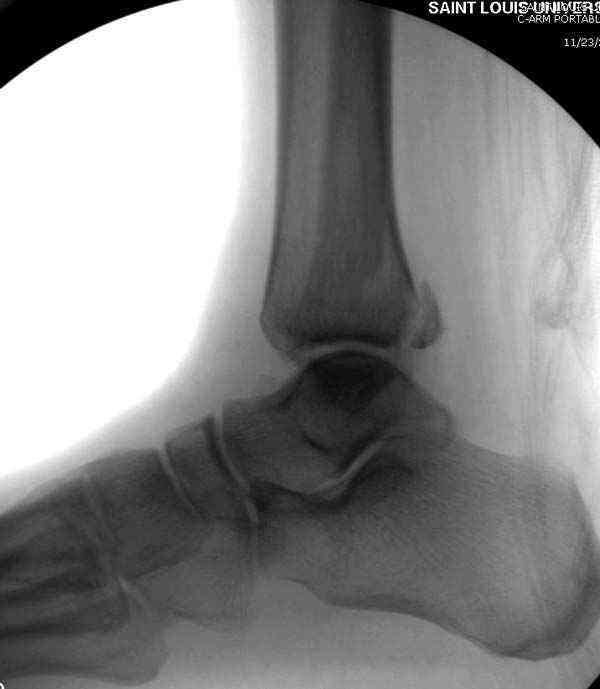

Здесь несколько частных случаев: перелом голеностопа со сравнительными снимками и разрыв синдесмоза, а также медиальная Hook пластина.

Нет первичных снимков, перелом очень низкий и под большим сомнением диагноз разрыва синдесмоза. Медиальная сторона отрепонирована на "хорошо" и, по-видимому, прорезание проволоки произошло во время операции. Без снимков трудно судить о высоте малоберцовой, а лодыжка находится в варусе. Лагирование получилось, но возле тонких шурупов передне-задний шуруп выглядит немного тяжеловато.

Во всех руководствах АО имеется описание техники применения низкопрофильных пластин 1/3 трубки, которые могут быть применены для фиксации наружной лодыжки. Фиксацию проводят кортикальными 3.5 мм шурупами, и если дистальная фиксация недостаточная, тогда усиливают конструкцию созданием hook plate. Сгибая конец пластины на последнем отверстии, внедряют его в дистальный отдел, и тем самым создается дополнительная фиксация.

Современные преконтурированные пластины не имеют таких недостатков, и разделяются на правые и левые, а также на латеральные и задние. Множественные дистальные шурупы 2.7 мм уменьшают подкожное раздражение, и такой имплант можно оставить на долгий срок без удаления.

Коллеги правы, что при рутинных переломах достаточным бывает обычные снимки с мортизом. А стрессовые рентгенограммы могут уточнить, есть ли разрыв синдесмоза.